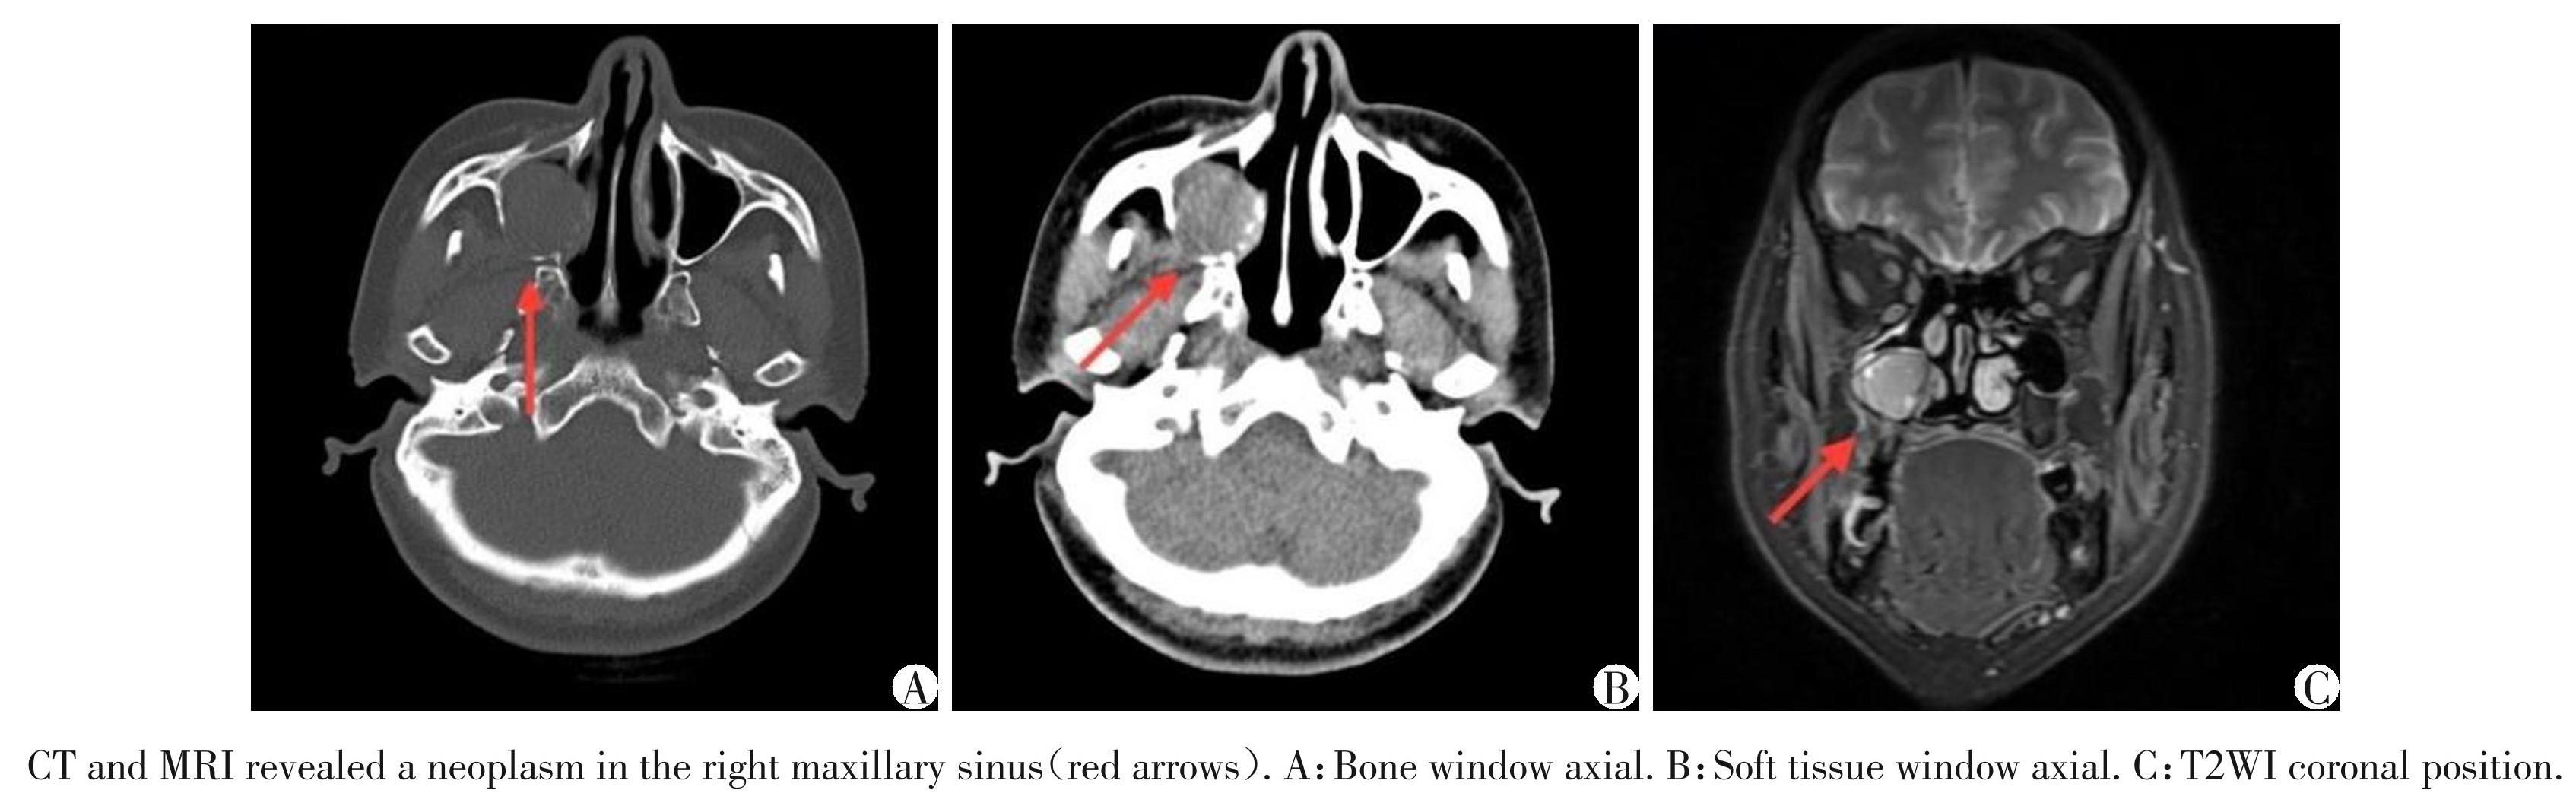

患者,女,67 岁,2023 年 7 月因“复查发现右侧上颌窦肿物”入院,既往患有干燥综合征及甲状腺功能减退症。2018年7月患者体检行CT检查发现右侧上颌窦、筛窦、额窦肿物,于外院行鼻内镜手术切除。术后常规病理报告示:涎腺源性肿瘤形态,以基底细胞肿瘤形态为主,灶性区伴肌上皮分化,部分呈腺样囊性癌形态,需补做免疫标记及检测人乳头瘤病毒(human papillomavirus,HPV),除外HPV 相关性多表型鼻腔鼻窦癌。免疫组化报告示:结合 HE 切片,符合涎腺源性肿瘤,类型难定,倾向基底细胞肿瘤伴局灶肌上皮分化及灶性区腺样囊性癌样形态。2019 年 8 月患者无明显诱因出现右鼻出血,查CT及MR发现右侧上颌窦新生物(图1),考虑肿瘤复发。于南京医科大学第一附属医院行鼻内镜下手术切除,术后病理及免疫组化提示低度恶性上皮源性肿瘤,诊断:①基底细胞腺癌;②腺样囊性癌(adenoid cystic carcinoma,ACC);③HPV相关性多表型鼻腔鼻窦癌;④非角化性鳞状细胞癌。 HPV PCR检查为阴性,排除HPV相关性多表型鼻腔鼻窦癌。患者术后接受 46 Gy 的放疗,分 23 次进行。术后定期随访,2023年7月复查CT、MR提示右侧上颌窦近翼腭窝处新生物(图2),未发现远处转移。再次行鼻内镜下手术切除,术后病理提示肿瘤复发(图3)。免疫组化提示 CK5/6(+),P63(+), Calponin(-),SMA(+),CD117(部分+),Ki67(热点区约40%+),P16(部分+),P40(+),CK8/18(+),S⁃100 (-),β⁃Catenin(膜+),C⁃myc(+),Bcl⁃2(+),EGFR (+)。采用MYB 基因分离探针检测提示MYB 基因断裂重排(图4);结合 HE 切片,符合实性型 ACC。历经5年3次手术最终明确病理诊断。现患者每隔 3个月随访,未见复发。

图1患者2019年8月术前CT及MR影像

Figure1Preoperative CT and MRI images of the patient in August 2019